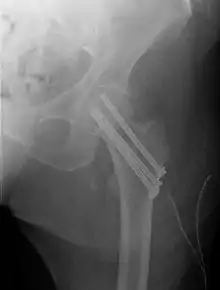

كسور ما بين النتوئين تحدث بين النتوء الأكبر والأصغر. وعادة ما تثبت باستخدام شريحه معدنيه ومسمار منزلق. الالتئام عادة ما يكون جيد عندما يكان المريض بصحة جيدة.

كسر ما بين النتوئين

وكسر ما بين النتوئين، تحت عنق عظم الفخذ، لديه فرصة جيدة للشفاء. العلاج يشمل تثبيت الكسر عن طريق شريحه ومسمار لتثبيت طرفين الكسر في مكانهما. يتم ادخال مسمار كبير في رأس الفخذ عبر الكسر، وتمتد الشريحه للأسفل على جسم عظمة الفخذ، مع وضع مسامير صغيرة لتثبيتها في المكان.

عادة ما يتطلب الأمر 3-6 أشهر لالتحام الكسر. ولأن هذا النوع من الكسر شائع فقط في كبار السن، فانه عادة لا ينصح بإزالة مسمار الورك لتجنب المخاطر غير الضرورية التي يمكن أن تحدث من العملية الثانية وازدياد خطر الكسر مره ثانيه بعد إزالة المسامير. السبب الأكثر شيوعا لكسور الورك في كبار السن هو هشاشة العظام، وإذا كان هذا هو الحال، فان علاج مرض هشاشة العظام يمكن أن يقلل أيضا من خطر المزيد من الكسور. في المرضى الشباب فقط نميل إلى إزالته، لأن الأجزاء المزروعه قد تعمل على زيادة الإجهاد على المفصل، ويزيد من خطر حدوث كسر في حالة حدوث حادث آخر.